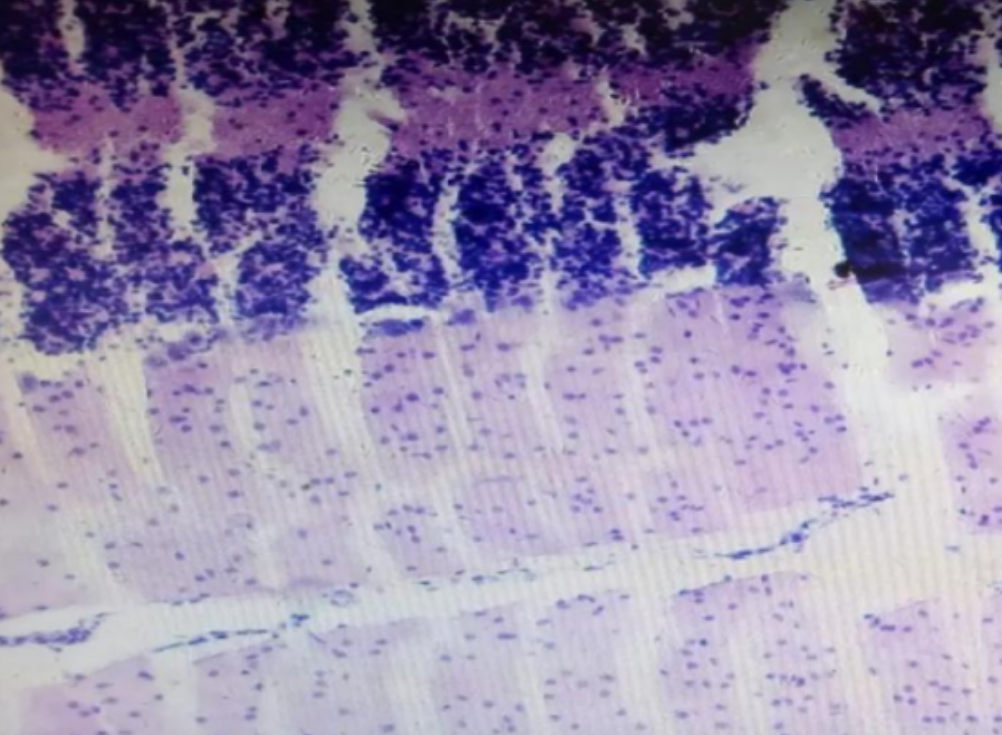

HE染色,全称苏木精-伊红染色法(Hematoxylin and Eosin staining),是最常见的组织切片染色技术之一,用于在显微镜下观察和分析组织或细胞的结构和形态。虽然HE染色是最常见且最基础的染色技术之一,😭但在实验过···

HE染色,全称苏木精-伊红染色法(Hematoxylin and Eosin staining),是最常见的组织切片染色技术之一,用于在显微镜下观察和分析组织或细胞的结构和形态。

虽然HE染色是最常见且最基础的染色技术之一,😭但在实验过程中,很容易出现各种情况导致染色切片质量参差不齐。所以,小编根据以往实验经验,给大家整理归纳出了15个HE染色中的常见问题,还包含问题原因分析以及解决方法哦~